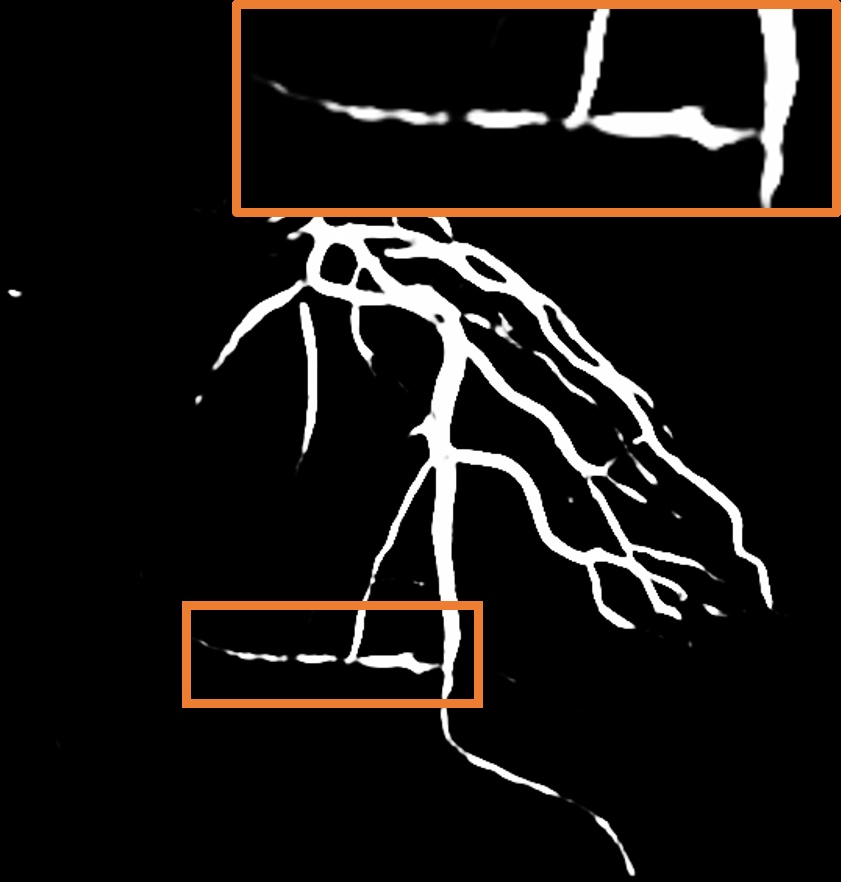

Layer separation bootstrapping.

To validate the effectiveness of the layer separation bootstrapping, we train foreground and background canonical images using the same representation. The results are shown in Table 2, where optimizing both foreground and background canonical images simultaneously leads to a decrease in the Dice score by 0.0055. The comparison is shown in Figure 8 (a), where the orange area indicates the difference between without and with Layer separation bootstrapping. The bottom-right corner shows a zoom-in patch, highlighting the significant effect of the bootstrapping step.

Hessian prior loss .

To test the effect of the Hessian prior loss, we remove the Hessian prior loss. As a result, the segmentation performance, as shown in Table 2, also decreases the Dice score by 0.0063. The comparison between the without and with is shown in Figure 8 (b), where the orange area indicates the difference between them. The zoom-in patch shows that our model predicts less noticeable vascular regions incorporating the Hessian prior loss .

Parallel vessel motion loss .

We conduct an experiment to assess the effect of the parallel vessel motion loss by removing it from the training pipeline. As shown in Table 2, the segmentation performance decreases the Dice score by 0.0047. Without this loss to enforce parallelism between blood and vessels, the segmentation results are negatively affected. In addition, the comparison between without and with is shown in Figure 8 (c). The zoom-in patch shows that the image with has clearer segmented vascular regions.